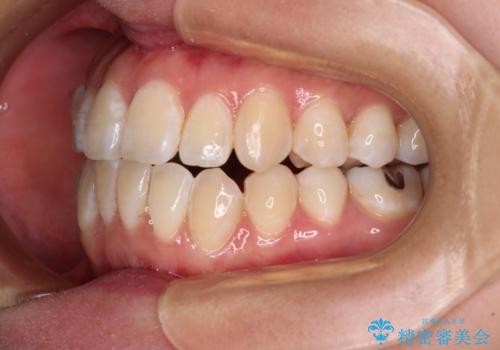

外に飛び出して磨きにくい奥歯と上下前歯の隙間 インビザラインによる矯正治療

- 上下前歯の隙間と、外側を向いていて歯磨きのしにくい奥歯を気にして来院された患者様です。

下顎前歯が1本欠損しており、上下アーチはアンバランスとなりますが、インビザラインを用いて上下の隙間を改善しながら歯列を整えることとしました。

外側を向いている奥歯は、内側にアンカースクリューを埋入して牽引の固定ゲント氏、部分的にワイヤー装置を用いることで歯列に納めることとしました。